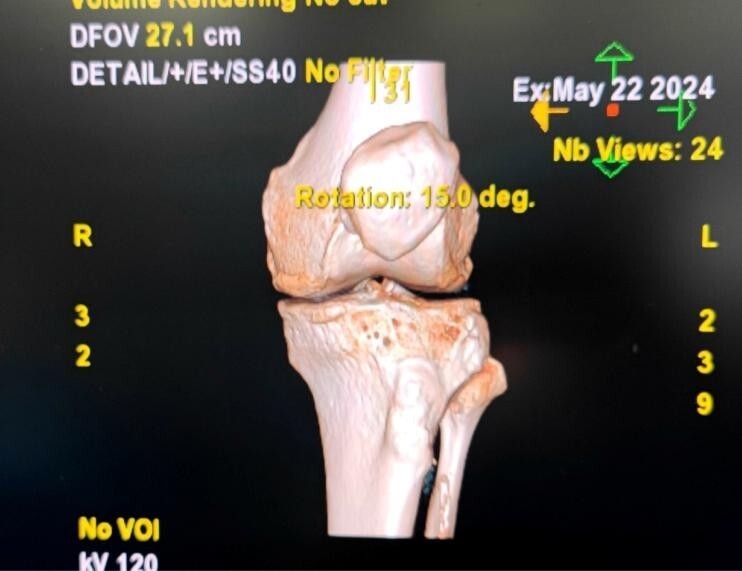

第1例:机器人辅助下全膝关节置换术

68岁的何先生因“左膝关节疼痛伴活动受限18年加重2个月”慕名来院就诊,经检查后手术治疗,经过仔细的术前评估,医生建议其选择机器人辅助下全膝置换手术,患者家属之前就在媒体上听说过机器人手术,考虑之后同意了手术方案。

23日上午9时许,手术开始,约2个半小时顺利完成手术,术后片子显示假体植入位置准确,目前患者各项情况良好。